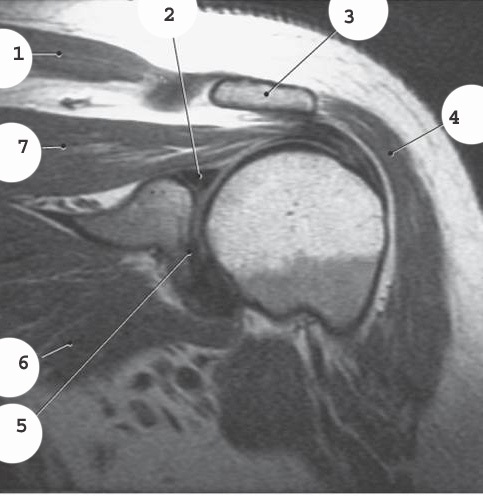

3

infraspinatus muscle

4

teres minor muscle

5

deltoid

8

subscapularis muscle

10

supraspinatus muscle